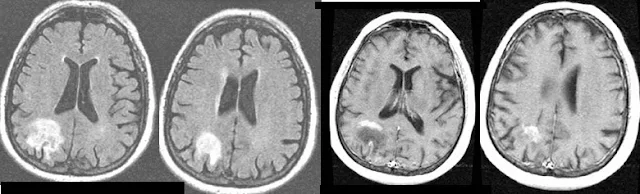

Hμιανοψία είναι η απώλεια του μισού οπτικού πεδίου στον έναν (ετερόπλευρη) ή και στους δύο (αμφοτερόπλευρη) οφθαλμούς. Διακρίνεται σε ετερώνυμη, οπότε χάνονται είτε τα εξωτερικά (κροταφικά) είτε τα εσωτερικά (ρινικά) μισά του πεδίου της όρασης, και σε ομώνυμη, οπότε χάνονται τα ομόπλευρα μισά (είτε δεξιά είτε αριστερά) του πεδίου της όρασης. Η ημιανοψία είναι αποτέλεσμα εγκεφαλικής αιμορραγίας, κρανιακών βλαβών ή εγκεφαλικών όγκων. Αν ο εγκεφαλικός ιστός δεν έχει καταστραφεί ολοκληρωτικά, η ημιανοψία είναι ανατάξιμη. Η απώλεια του οπτικού πεδίου συνήθως σημαίνει την τύφλωση για όλα τα είδη των οπτικών ερεθισμάτων, αν και μερικές φορές μπορεί να χαθεί η ικανότητα, παραδείγματος χάριν, αντίληψης του σχήματος ή ενός αντικειμένου, αλλά να διατηρηθεί η ικανότητα αντίληψης χρώματος, φωτός και κίνησης στο ίδιο οπτικό πεδίο. Επίσης, μπορεί να μην αφορά πλήρως το μισό οπτικό πεδίο (ατελής) ή να αφορά μόνο ένα τεταρτημόριο του.

Η ημιανοψία δείχνει βλάβη στο οπίσθιο μέρος του εγκεφάλου που είναι υπεύθυνα για την όραση και συχνά προκύπτει από εγκεφαλικό επεισόδιο ή τραυματική εγκεφαλική βλάβη